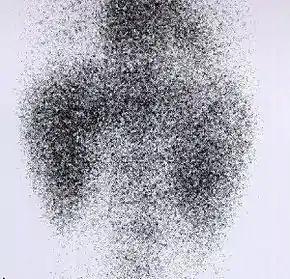

![]() Decreased Tc99m-DMSA uptake in both kidneys, suggestive of renal failure. | |